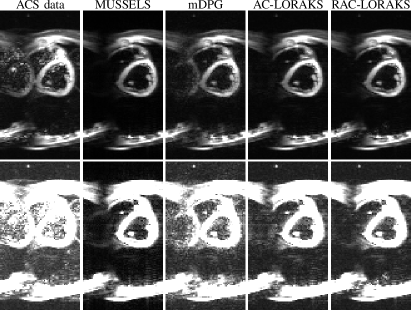

Finally, Fig. 8 shows results from the in vivo cardiac EPI data. While this data was not accelerated (), this case is challenging because of the double-oblique slice orientation as well as the substantial artifacts present in the ACS data resulting from cardiac motion-induced shot-to-shot variations. In addition, this case can also be challenging for SENSE-based methods (like MUSSELS), due to the use of a small FOV with aliasing. When aliasing is present within the FOV, it violates the standard SENSE modeling assumption of one sensitivity map value per spatial location, which generally leads to artifacts if not properly accounted for. The results demonstrate that both MUSSELS and mDPG have substantial residual ghosting artifacts, which might not be surprising given the high degree of corruption that is present in the ACS data. On the other hand, both AC-LORAKS and RAC-LORAKS are more successful at suppressing the ghosts. Without a gold standard reference, it is hard to establish definitively whether AC-LORAKS or RAC-LORAKS is better in this example, although we believe that the RAC-LORAKS result demonstrates slightly less ghosting than AC-LORAKS, particularly on the left side of the image where the ACS data and mDPG both have particularly strong ghost artifacts.

Figure 8: ACS data and reconstruction results for unaccelerated in vivo cardiac EPI data. The two rows show the same results, but the second row has 5 intensity amplification to better highlight the ghosting characteristics.